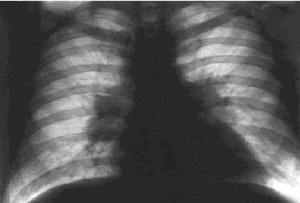

Рис. 1. Рентгенограмма грудной клетки больного саркоидозом внутригрудных лимфатических узлов. Корни легких расширены, значительное двустороннее увеличение внутригрудных лимфатических узлов, преимущественно бронхопульмональных. Умеренно выраженное усиление легочного рисунка в прикорневых отделах.